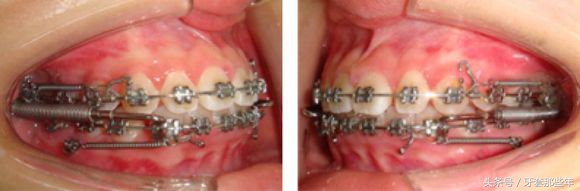

打了骨钉,用金属托槽进行矫正

治疗后,面形不再显得凸起,唇部形态得到了极大的改善